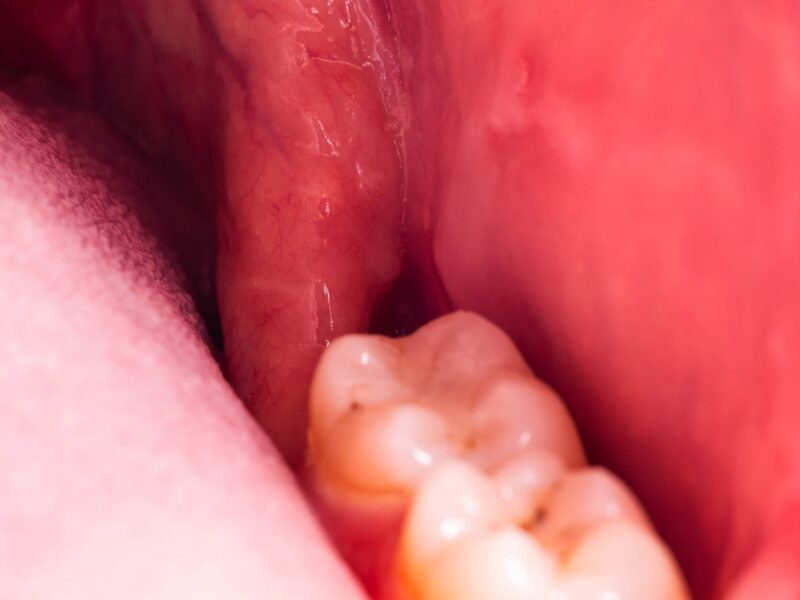

症例紹介

親知らずの抜歯や顎関節症の治療では、患者様の不安や症状にしっかり寄り添いながら、安心・安全な治療を提供しています。

「難しいと言われた親知らず」「顎の不調が治らない」などのお悩みは、ぜひ一度、当院へご相談ください。